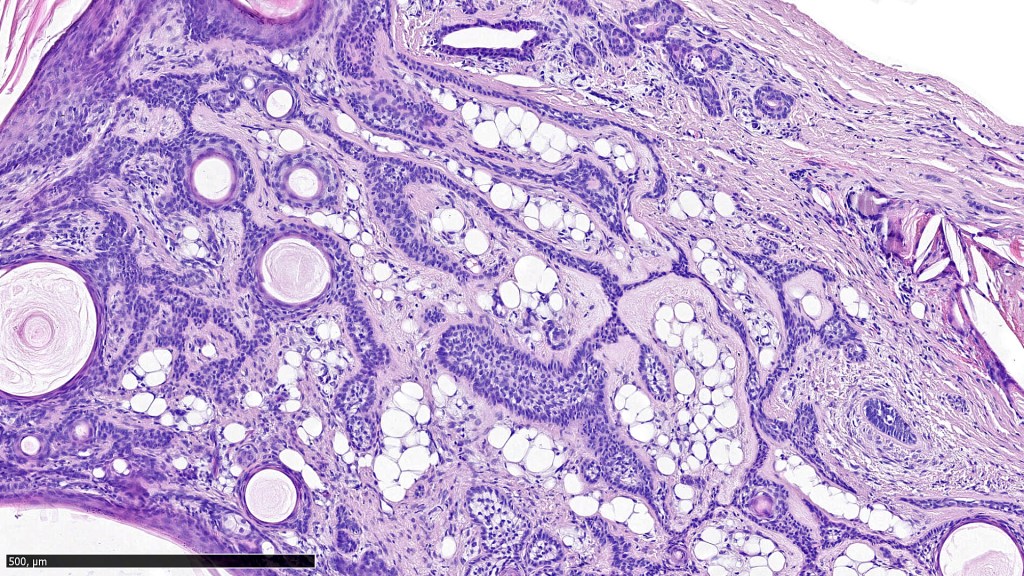

•Well circumscribed unencapsulated, nodular/multinodular silhouette composed of an admixture of epithelial & mesenchymal elements

•Mixed epithelial component including nests & cords of epithelium with abundant, eosinophilic cytoplasm & small vesicular nuclei

•Glandular differentiation sometimes showing apocrine differentiation

•Myoepithelial layer in glandular foci

•Ductal differentiation

•Plasmacytoid myoepithelial cells; clear cell change

•Follicular & sebaceous differentiation

•Myxoid change